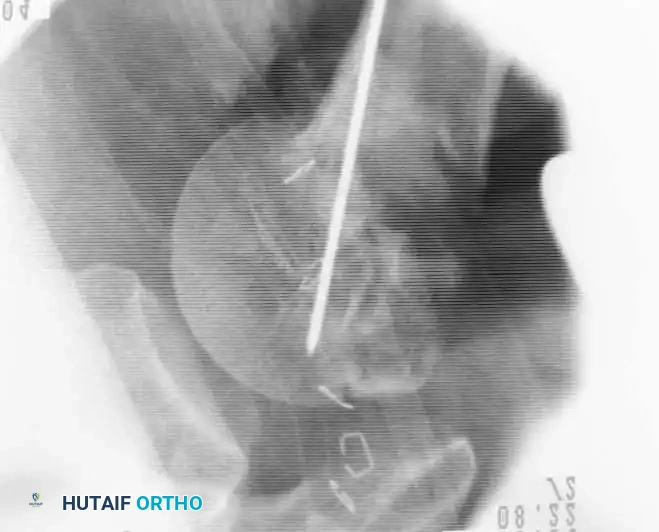

Open Reduction and Internal Fixation (Locked Plating)

For complex three- and four-part fractures, particularly in patients with osteoporotic bone, proximal humeral locking plates have revolutionized treatment. These fixed-angle constructs provide superior biomechanical stability compared to conventional non-locking plates.

Surgical Approach:

* The deltopectoral approach is the workhorse for proximal humeral ORIF, utilizing the internervous plane between the deltoid (axillary nerve) and pectoralis major (medial/lateral pectoral nerves).

* The cephalic vein is identified and typically retracted laterally with the deltoid to protect its tributaries.

Fixation Principles:

* Anatomic reduction of the medial calcar hinge is critical to prevent varus collapse.

* Heavy nonabsorbable sutures are passed through the rotator cuff tendons and tied to the plate to neutralize tuberosity pull.

* Locking screws are placed into the humeral head, ensuring they do not penetrate the articular surface (subchondral placement is ideal).